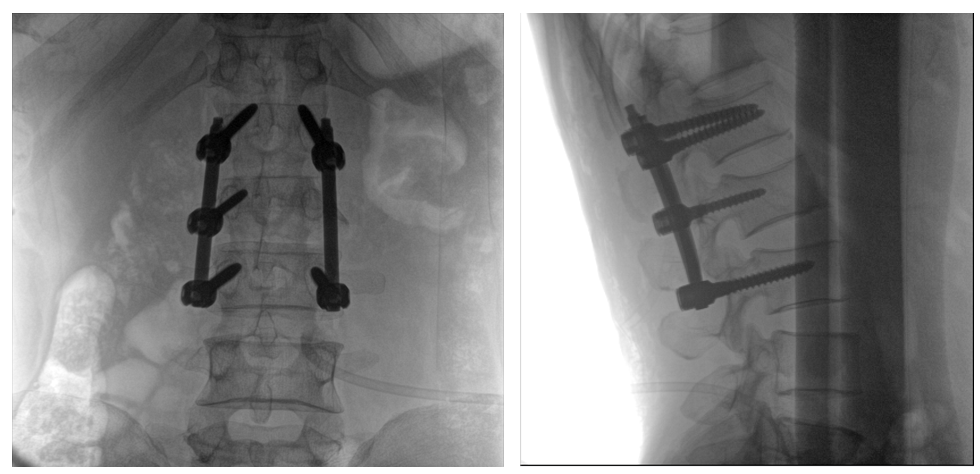

病例一:

患者不慎摔傷,傷后腰部疼痛,腰2椎體壓縮性骨折,遂以“椎弓根釘內固定術”治療。椎弓根螺釘可以從椎體后方貫穿到椎體前方,達到椎體三柱固定,但是手術過程中要保對多節錐體進行手術,所以要求圖像要盡可能的展現出全節段腰椎。

一體式C形臂全節段腰椎臨床影像

普愛醫療PLX119C大平板一體式C形臂采用30CM×30CM的平板探測器,一般可一次性成像5節腰椎,呈現更廣闊的視野。使醫生一次性全面地觀察到傷椎及周圍椎體情況,使得手術效率更高、更準確。